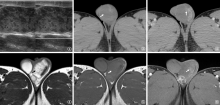

男性生殖系统结核(male genital tuberculosis,MGTB)可发生在男性生殖系统的各个器官,MGTB临床症状不典型或无临床症状,容易造成漏诊和误诊,随着医学影像学技术的发展,影像学表现在MGTB的诊断和鉴别诊断中有着重要的作用。作者旨在系统归纳男性生殖系统各个器官结核的超声、计算机断层扫描(computed tomography,CT)和磁共振成像(magnetic resonance imaging,MRI)的表现,提高对MGTB的认识和临床诊断能力。

| [11] | 李翔, 马仲序, 付旭文, 等. 56例附睾结核CT影像表现分析. 中国防痨杂志, 2022, 44(10):1100-1103. doi:10.19982/j.issn.1000-6621.20220208. |

| [17] | 张秀丽, 苏航, 陈争光, 等. 二维超声联合微血管血流成像对睾丸结核的诊断价值. 郑州大学学报(医学版), 2024, 59(5):715-718. doi:10.13705/j.issn.1671-6825.2024.04.061. |

| [18] | 边巴次仁, 次旦旺久, 任翠, 等. 睾丸肿瘤与结核的CT表现分析. 国际泌尿系统杂志, 2025, 45(1):77-80. doi:10.3760/cma.j.cn431460-20230712-00019. |

| [19] | 侯民羊, 苟杰. 睾丸结核的CT诊断. 中国医学影像学杂志, 2010, 18(4):381-383. doi:10.3969/j.issn.1005-5185.2010.04.016. |

| [20] | 闫瑞芳, 李学坤, 张改云, 等. MRI诊断附睾睾丸结核. 中国医学影像技术, 2020, 36(10):1517-1520. doi:10.13929/j.issn.1003-3289.2020.10.020. |

| [21] | 王唯伟, 寻静, 项梅, 等. 睾丸结核的MRI表现1例. 医学影像学杂志, 2021, 31(10):1780, 1784. doi:10.3760/cma.j.cmcr.2022.e05195. |